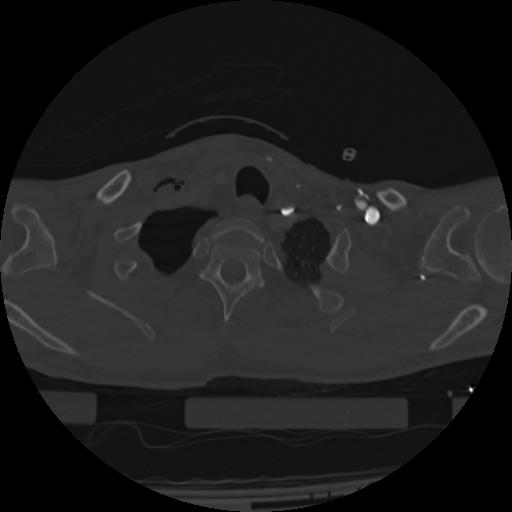

22 ANGIO,CE,Vol,0.5,ANGIO,,